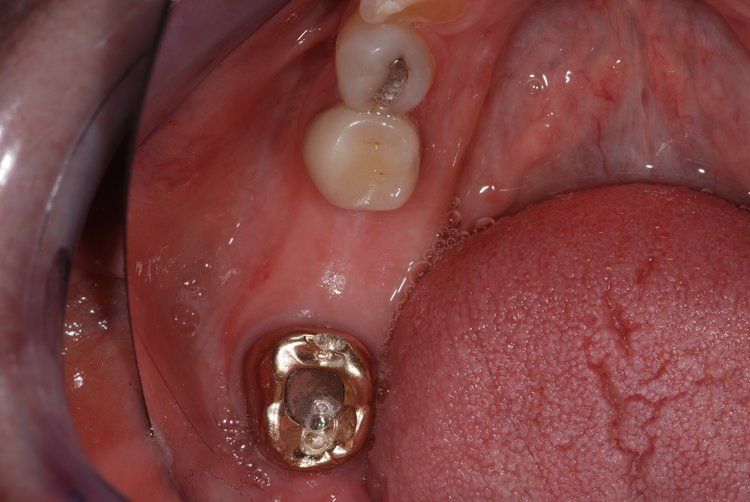

Unfortunately, it can be the case that a tooth (or teeth) are so badly damaged by trauma, bacteria, or tooth decay that removal is the only option. In this case, we recommend that a patient has dental implants inserted to replace any missing teeth. Modern dental implants are long lasting, strong, and look, feel, and function just like real teeth.

At the Dental Innovations clinic in Wasilla, AK, we specialize in single and multiple implant restorations. Our team can use a wide range of implant systems to provide patients with a full mouth of even, strong teeth. Contact our dental clinic today to arrange a consultation to discuss what dental implants may be the best for you.